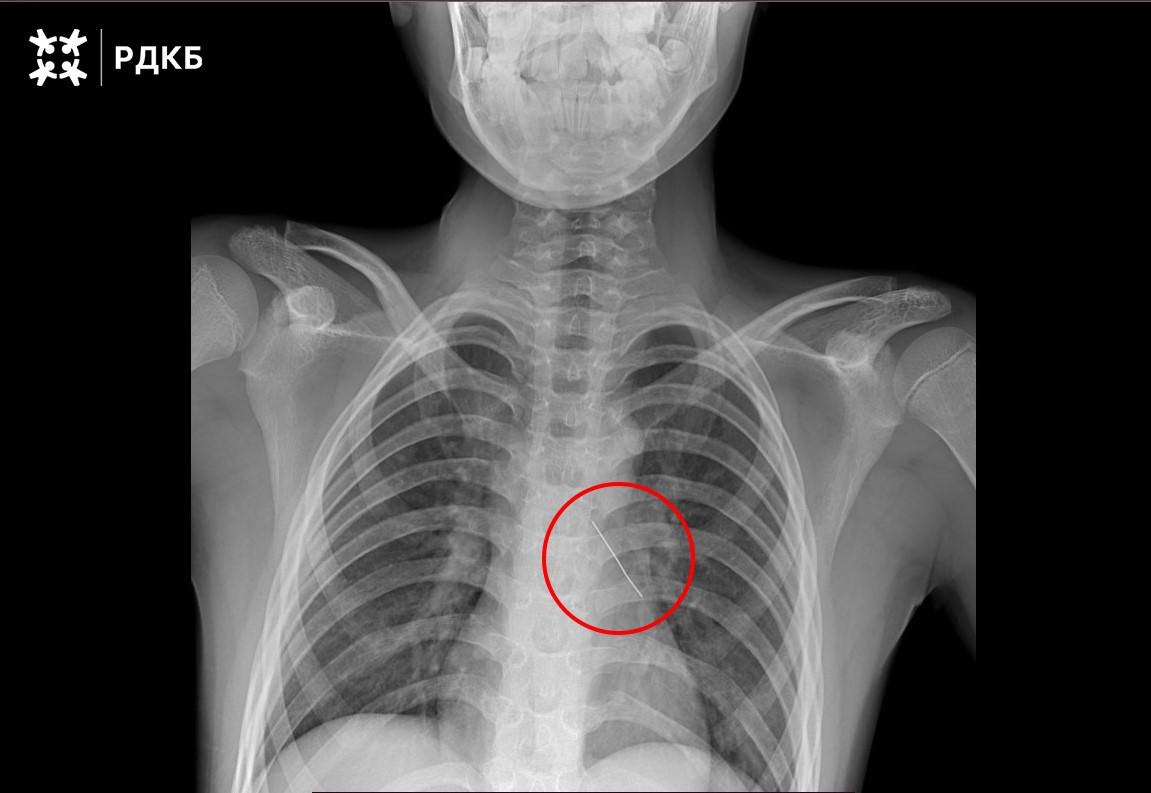

Обычная французская булавка может, как выяснилось, не только что-то приколоть, но и причинить очень серьезный вред. 11-летний мальчуган, проглотив ее, чуть не умер - острый предмет пронзил бронх, что могло спровоцировать коллапс легкого. Ребенок мог говорить только шепотом и жаловался на боль в груди. Извлекать булавку пришлось врачам Республиканской детской клинической больницы. Все прошло без осложнений. 1